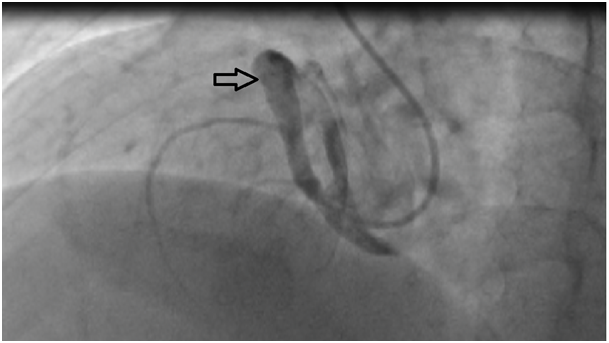

27years old male patient admitted to our outpatient clinic with progressive, pleuritic chestpain unrelated to exertion for a month with no significant medical history. The patient was diagnosed with acute pericarditis at an center and receiving ibuprofen and colchium treatment for three weeks. There was no pathological finding on cardiacaus cultation, blood pressure was 110/80mmHg, heart rate was 110bpm. Electrocardiography showed sinustachicardia and minimal ST segment elevation in all leads. There was a slight cardiomegaly in chest X-ray (Figure 1). Cardiac markers and inflammatory marker were elevated; troponin-I 1112ng/L (0-100), CK748 U/L (0-190), CK-MB 95 U/L(3-25), ESR 65, CRP 75 was detected. Transthorasic echocardiography revealed a 45x60 mm of cavitary mass compressing the right atrial free wall along with pericardial effusion (Figure 2); which was the only location of pericardial effusion in his previous examination a month ago. The patient was admitted to CCU. An aneursym 100x70x60mm in diameter, originating from right coronary artery extending to right atriallateral wall border and compressing externally, which contains thrombus material in its cavity was detected in cardiac computed tomography (CT) (Figure 3). Coronary angiography revealed a giant aneurysm communicated with RCA (Figure 4) without any abnormalty on left coronary arteries. The patient was given to emergency surgery because of the risk of pericardial tamponade. Aneurysmectomy was done and the remained cavity was closed primarily. Pathological examination was reported as polymorpho nuclear leukocyte and mononuclear inflammatory cell infiltration without elastic fibers and a pseudoaneursym of the coronary artery. The patient was discharged without any complication.

Figure 1 Cardiomegaly in chest X-Ray.